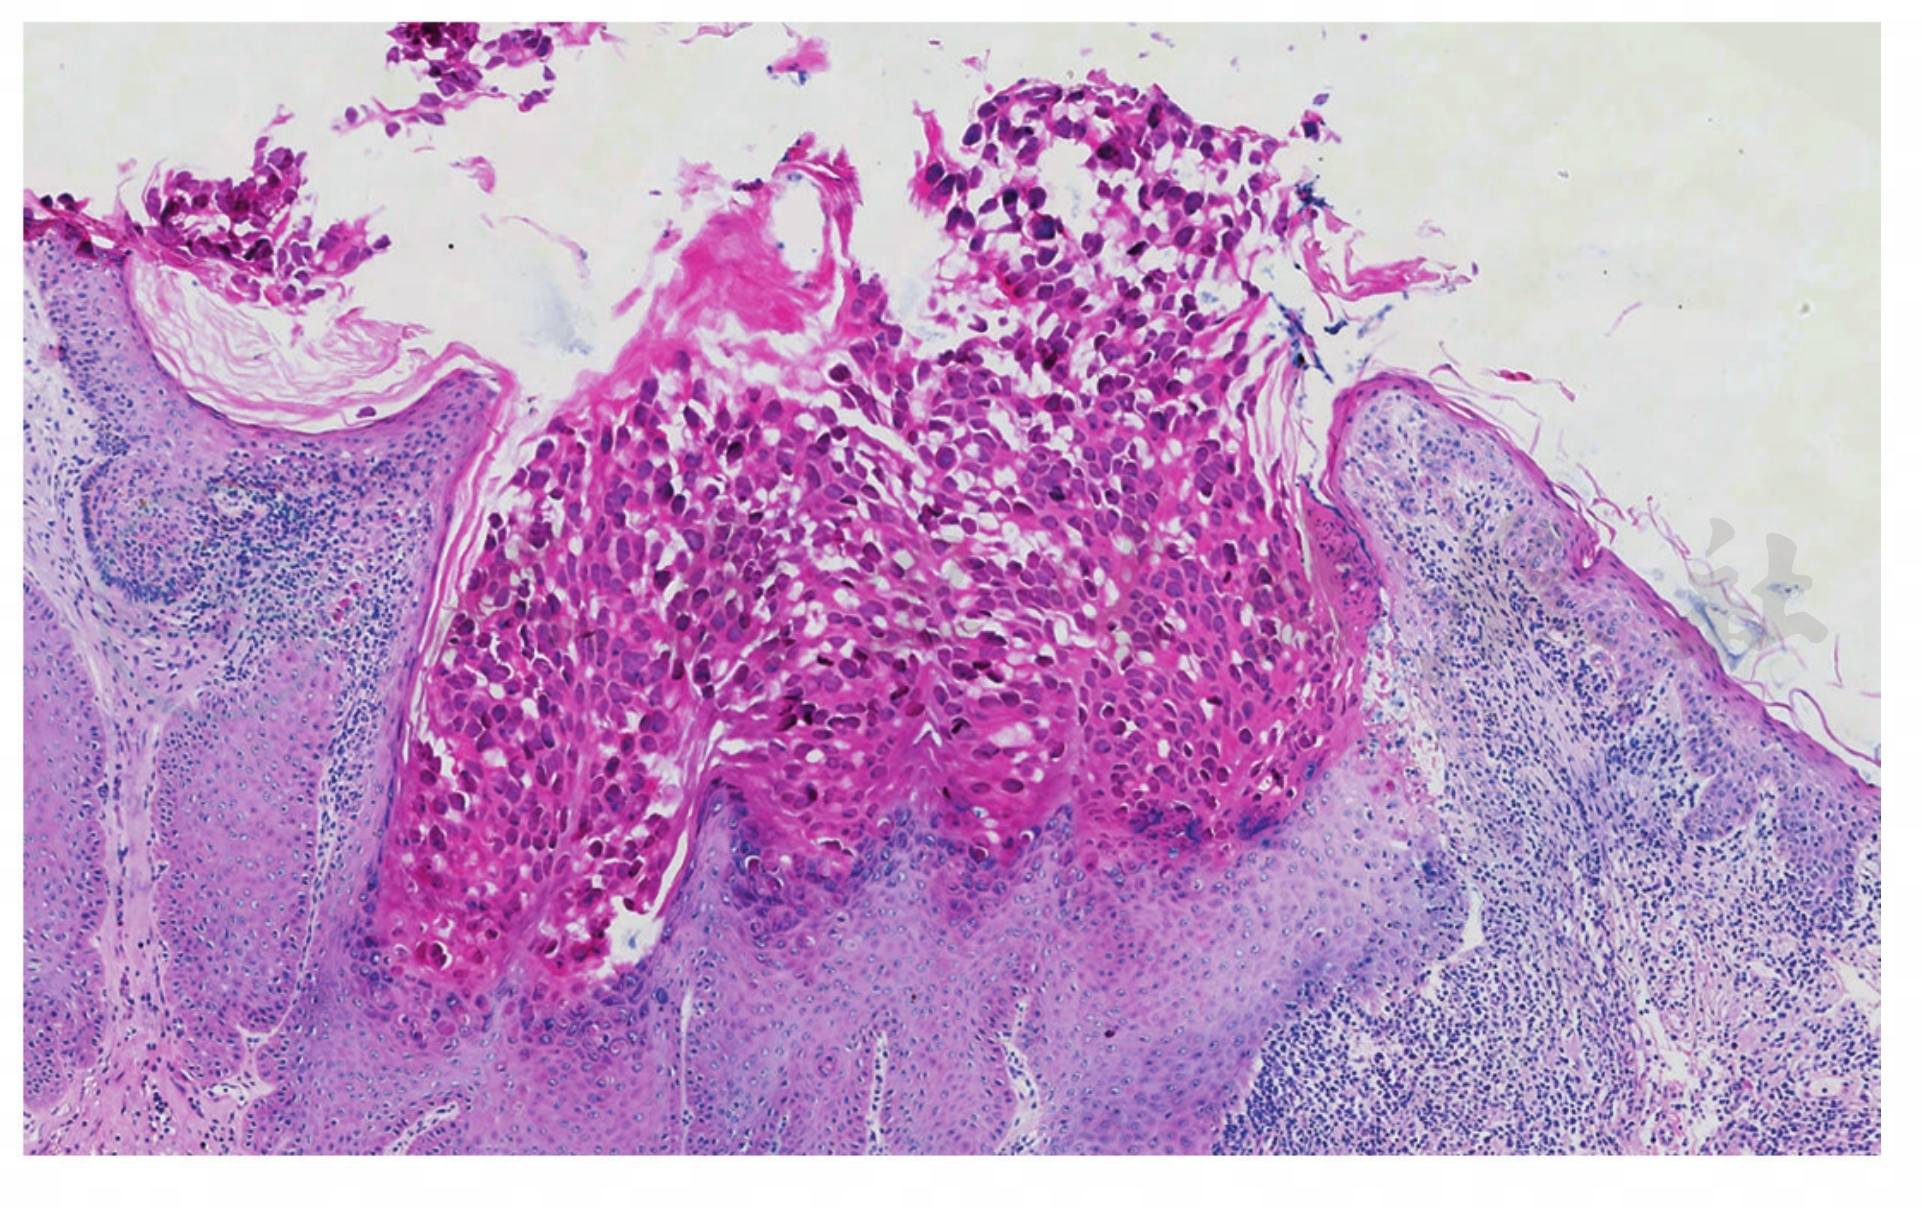

表皮角质细胞的胞质内有大的包涵体(软疣小体或Henderson⁃Patterson小体),随着它向皮肤表面移动,其体积逐渐增大(图1、图2)。

图2传染性软疣。角质层及颗粒层内大量软疣小体(HE 染色,×200)

引自:协和皮肤临床病理学.第1版.ISBN:978-7-117-28737-1.主编:

特征性的是表皮细胞内出现多数细胞质内包涵体,称为软疣小体。其小体挤压每个受损细胞的细胞核,使胞核呈弯月状,位于细胞的边缘;软疣小体由嗜伊红变成嗜碱性,在角质层可见多数35μm直径大小的嗜碱性软疣小体,若中心的角质层破裂,排出软疣小体,形成有中心的火山口样。毛囊性传染性软疣,真皮内有多数扩大的毛囊,其中充满了软疣小体。